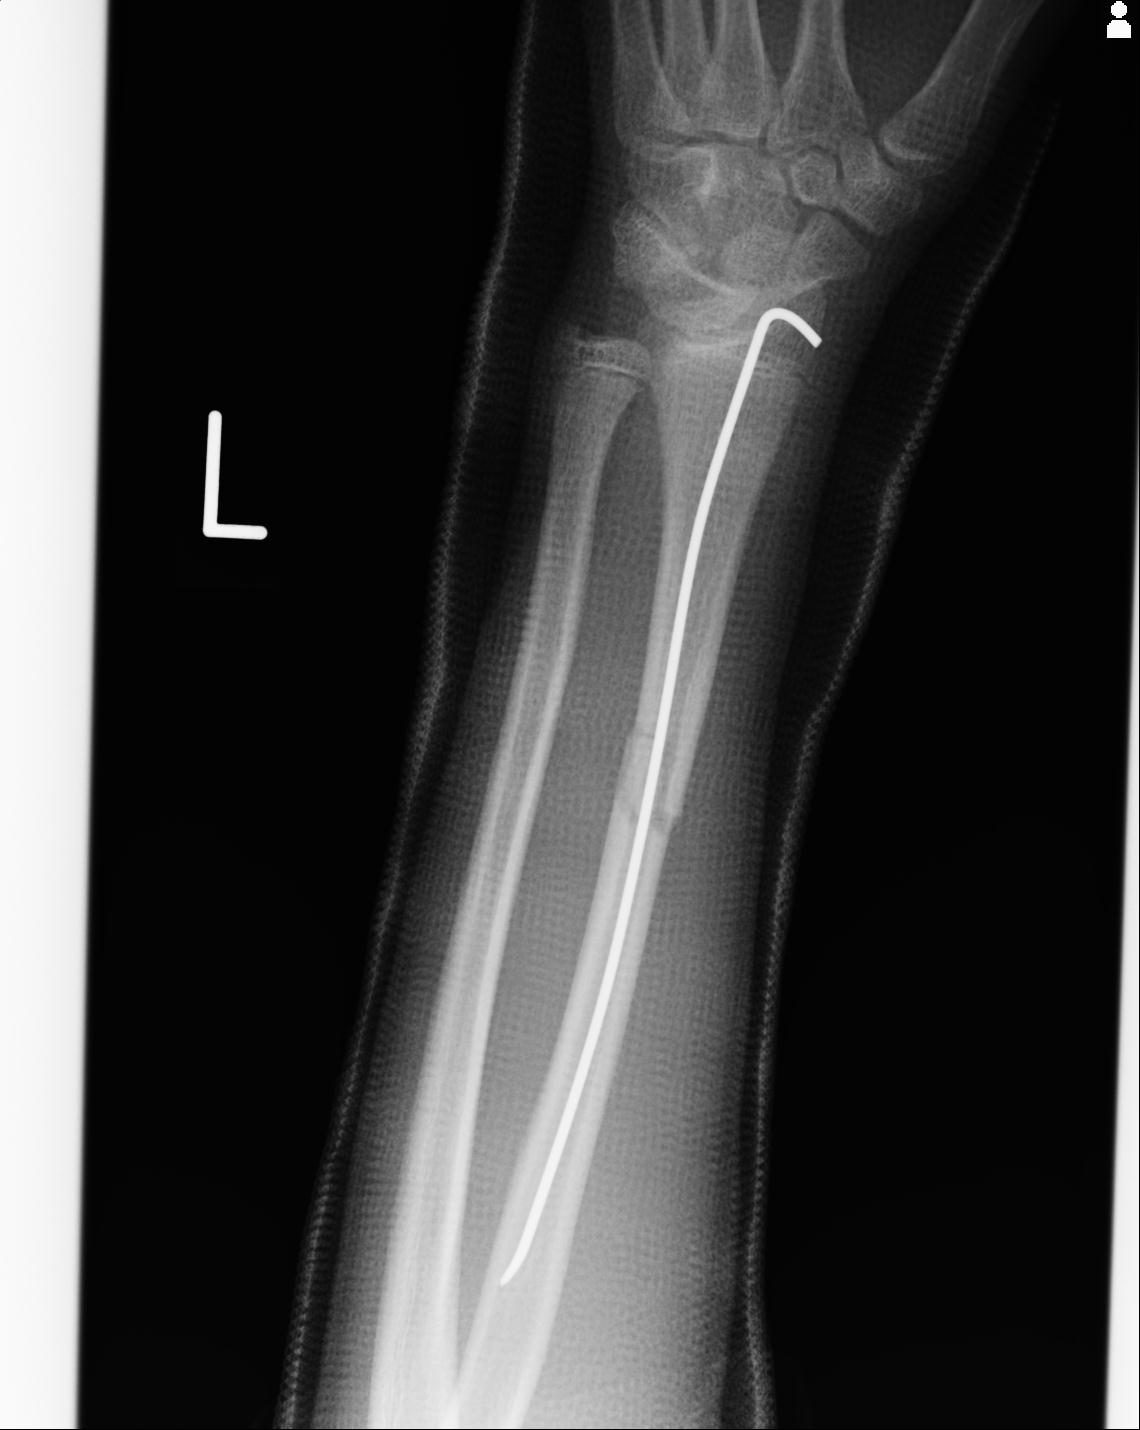

110211 1/6 1/8 左前腕 4R 15歳男性 橈骨骨幹部骨折

101290 1/4 5/21 5/20 手関節 2R 17歳男性 橈骨遠位端